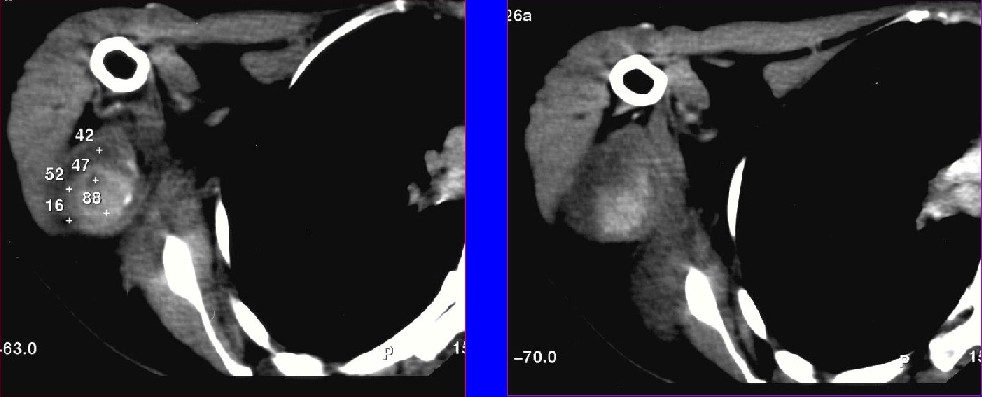

软组织肿瘤